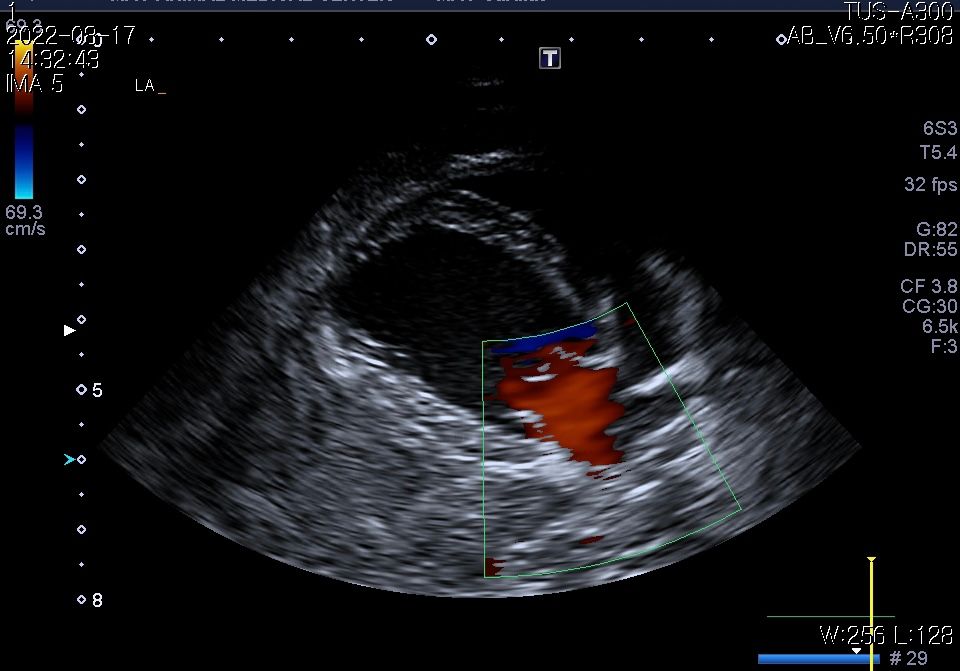

강아지 폐종양 의심되는데 봐주실 수있을까요?

11살강아지 입니다.

폐에 종양의심소견이 보인다고 해서요.

7월부터 기침을 간헐적으로 하다가 최근 심해져서 병원에 갔는데 엑스레이 상 폐종양이 의심된다고 해서요.

첨부해주신 사진만을 기초로 볼때 폐종양인 경우 좌측 폐전엽부의 종양이, 폐종양이 아닌 경우 종격동내의 종양 특히 흉선종양의 가능성이 높아 보입니다.